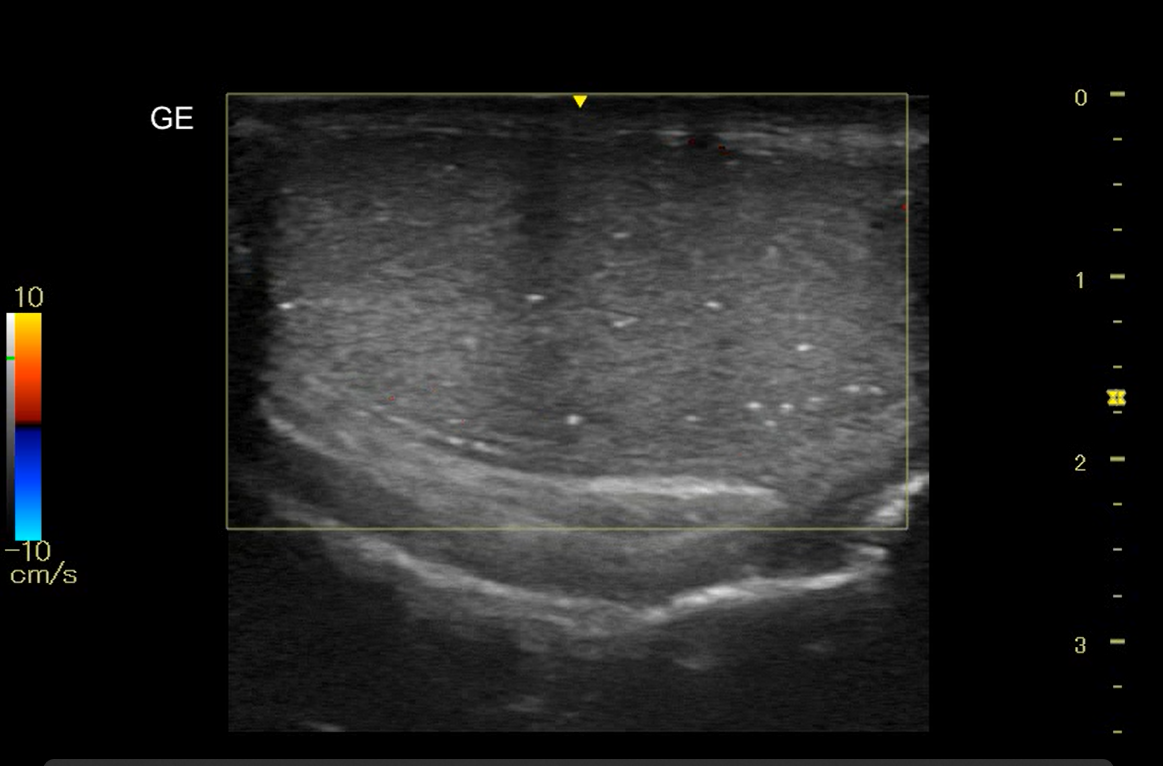

Realizamos ecografía clínica testicular: observamos ambos testículos con microlitiasis bilaterales puntiforme sin sombras acústicasen, en forma de cielo estrellado, vascularización normal, cabeza epidídimo izquierdo con leves signos inflamatorios, mínimo hidrocele.

Microlitisis testicular bilateral en contexto de Orquiepidimitis aguda. Diagnóstico diferencial con tumor testicular, torsión testicular, absceso testicular, hidátide.